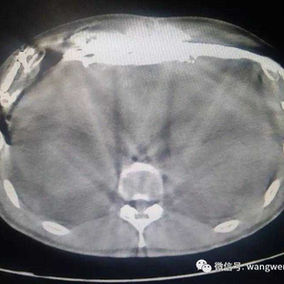

Preoperative Examination

The chest wall exhibits a large area of prominent and bilaterally symmetrical protrusion, predominantly in the upper half. There are also mild depressions on both sides of the lower half of the chest wall.

First, two 3 cm incisions were made on each side of the chest wall, followed by a 2 cm incision along the old surgical scar in the middle of the chest wall. Two bars were then placed on the protruding bone structures of the chest wall to perform the Wenlin procedure. Since the anterior chest wall is a rigid whole, correcting and pressing down the protrusion in the upper chest often causes a secondary depression below it. To address this, a third bar was inserted into the chest cavity to perform the Wung procedure, thereby elevating the depressed areas. Ultimately, the patient’s chest wall deformity was corrected, and the surgery achieved a satisfactory outcome.

In this case, the patient presented with a severe protruding chest wall accompanied by a slight depression. To achieve a better correction, the Wung procedure was performed subsequent to the Wenlin procedure, so that the concave deformity can be corrected as well.